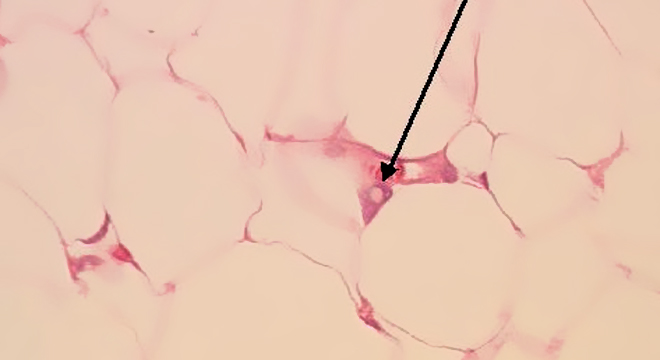

Das Lipom wird meist durch die genaue Inspektion der Haut und das Ertasten des Knotens, ohne zusätzliche Untersuchungen, erkannt. Manche potenziell gefährliche Hautverdickungen können einem Lipom jedoch ähnlich sehen, weshalb eine Untersuchung beim Hautarzt angezeigt ist. Bei Unsicherheit kann eine Biopsie mit Untersuchung des Gewebes erfolgen. Wird der Knoten chirurgisch entfernt, erfolgt auf jeden Fall eine histologische Untersuchung. Damit kann die Gutartigkeit des entfernten Materials bestätigt werden.